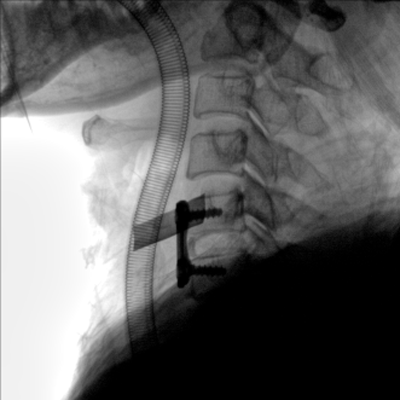

大尺寸動態(tài)平板探測器,高DQE、低噪聲、圖像清晰。采用多分辨率圖像增強(qiáng)處理技術(shù),不同部位不同圖像處理算法,滿足客戶多樣化的需求。

圖形化操控界面設(shè)計:設(shè)有多種人體特征攝影參數(shù),操作簡便。雙向紅光十字定位系統(tǒng):實現(xiàn)無射線下的高效定位。信息共享:遵循DICOM3.0格式接口,可無縫對接云PACS系統(tǒng)。